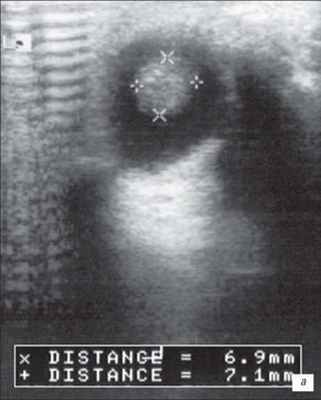

На первом месте по простоте использования и быстроте получения информации стоит УЗИ. Исследование позволяет достаточно быстро отдифференцировать ретинобластому от неопухолевых образований. Ретинобластома имеет характерные ультразвуковые признаки. При А-сканировании определяется высокоамплитудный эхосигнал с аттенуацией в нормальных тканях орбиты. По нашим данным, при В-сканировании с частотой излучения не менее 5-7 Мгц визуализируется округлое или неправильной формы внутриглазное образование с отложениями кальция. Образование исходит из задних отделов глаза, хорошо отграничено от стекловидного тела (рис. 1). Кровоток в опухоли не определяется. Эхографические исследования особенно показаны в динамике для оценки реакции опухоли на радиотерапию. Ультразвуковая картина опухоли весьма близка к так называемым псевдоопухолям сетчатки - гранулематозном изменении сетчатки, например, при токсокарозе. Безапелляционное заключение в совокупности с некритическим восприятием картины глазного дна по данным офтальмоскопии может привести к абсолютно не показанной энуклеации.

а) Небольшая ретинобластома. В ткани опухоли видны более плотные мелкие структуры (включения кальция).

Ультразвуковое В-сканирование. Крупные, кальцифированные опухоли проявляются как отдельные, овальные, солидные массы с чёткой передней границей.